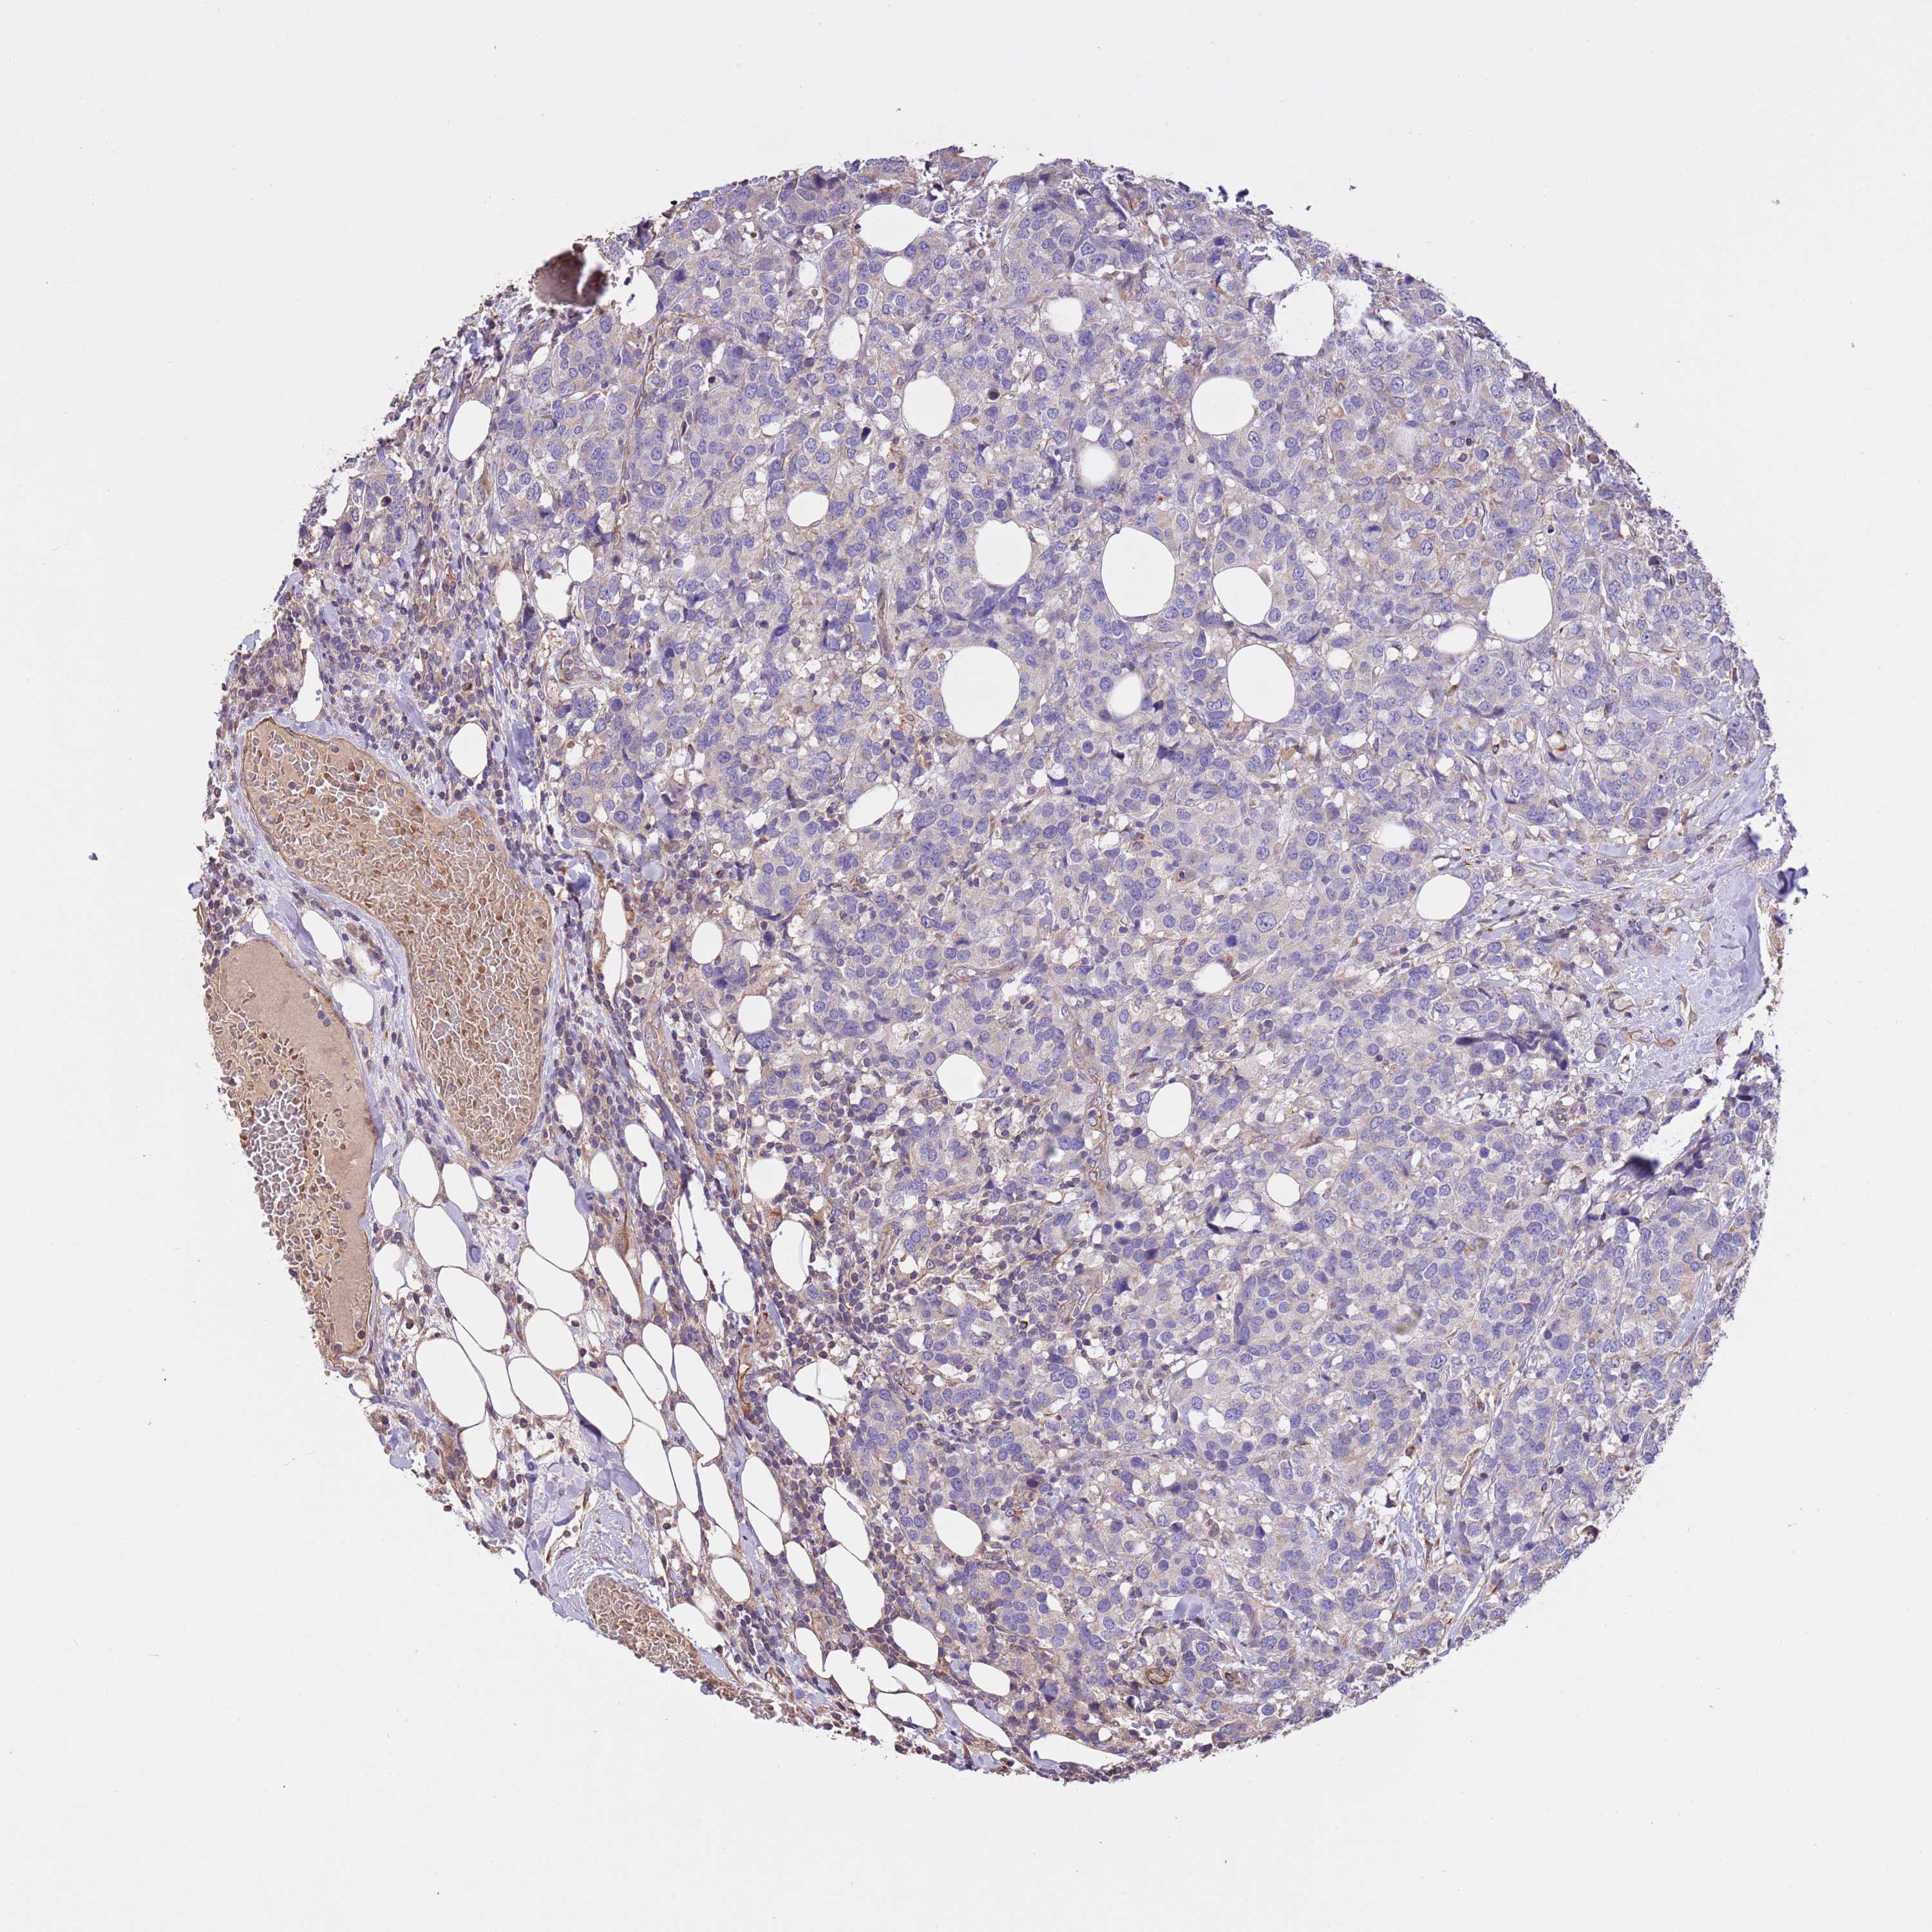

CANCER BREAST CANCER Show tissue menu

BRCA TCGA BRCA VALIDATION PROTEIN EXPRESSION

Breast cancer

Human cancer

Breast invasive carcinoma